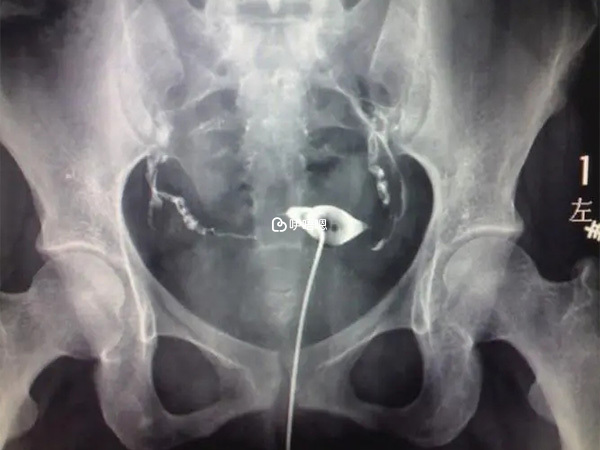

2018年2月,我們去醫院諮詢有關檢查流程的時候,醫生建議我也先去做個輸卵管造影,排除輸卵管堵塞造成女方不孕的問題,4月份我便去做了輸卵管造影檢查,結果顯示輸卵管雙側通而欠暢,那個時候只有那麼絕望了。我怕試管各種檢查、打針的痛,更怕要請假花很多時間和精力反覆去醫院。

我們決定試一下,週末去了深圳人民醫院,把情況給坐診的醫生說了,也給他看了造影的片子。醫生說輸卵管不通暢吃中藥可以解決,然後就給我開了中藥,每次開一個月的,並告知我可以邊吃藥邊嘗試懷孕,在沒發現懷孕之前藥要一直吃,所以我從5月底一直吃到8月初,而老公一直堅持吃他買來的精速活和蛋白鋅硒。